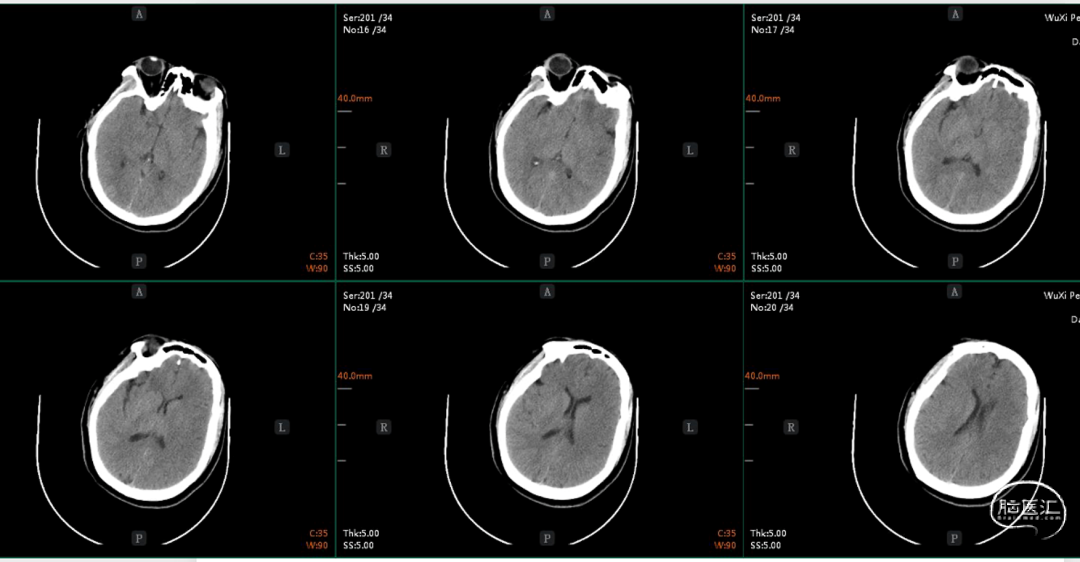

术前平扫CT:未见明显异常。

术前CTA+CTP:术前CTA可见左侧后交通动脉开放,左侧颈内动脉末端、大脑前动脉和大脑中动脉显影,左侧颈内动脉C6近端、大脑中动脉M1远端未显影。左侧颈内动脉区域CBF下降,CBV大致正常,MTT、TTP延长。

左右滑动查看更多